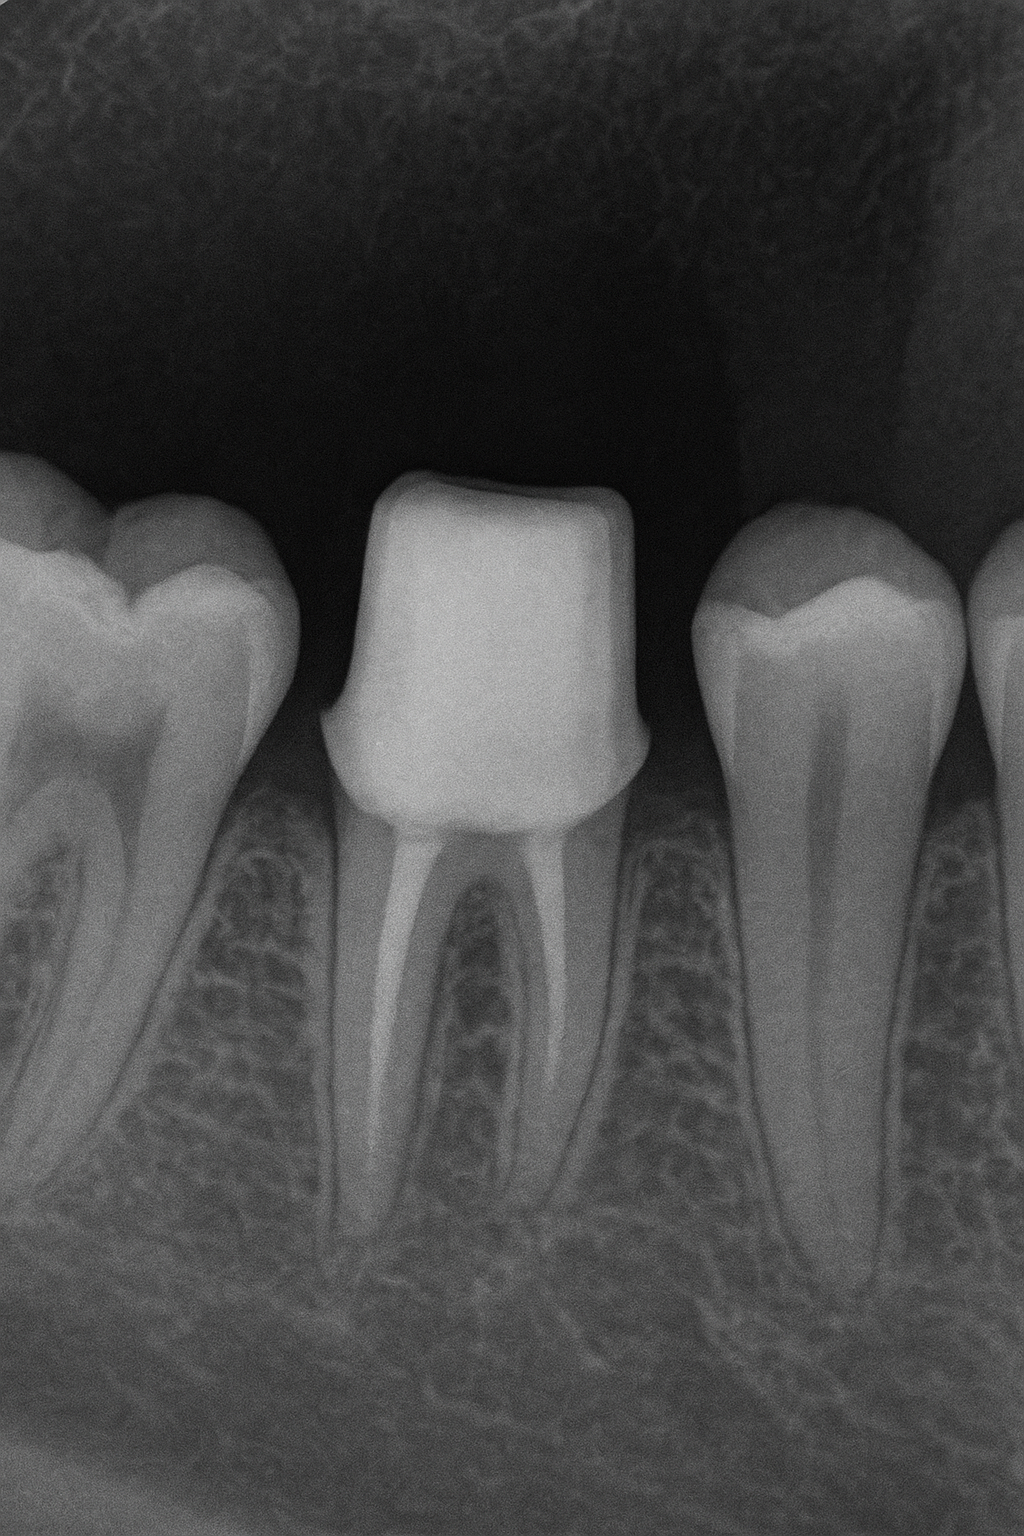

Dental X-ray of a tooth prepared for a crown in Winchester, VA.

First visit: Your dentist will take a look at the tooth, take X-rays if needed and get the tooth ready by removing any damaged bits. An impression or digital scan is taken to accurately analyze the teeth, roots, bone structure, and gum tissues for precise treatment planning, and a temporary crown is fitted to protect the tooth while the permanent crown is made. During the first visit, the dentist examines the tooth and takes X-rays to check the roots and surrounding bone.